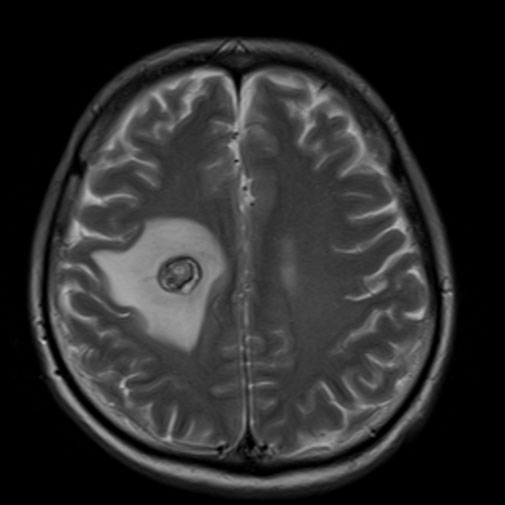

で、どうすりゃいのか、ってェと、グリセオールという脳浮腫の抑制治療薬を点滴し、あと6~9ヶ月間の経過観察で沈静化するのを待てばよい。安心したと言えば安心したンだが、すなわちこの先6~9ヶ月間も左半身の麻痺が続く……、って事になる。麻痺との闘いが新たなる闘いって事なんだが、抗ガン剤の副作用で出ている痺れと麻痺に加えてのダブルパンチ。しかも自分の冒されているガンは、進行度、転移再発度バリ高の超悪性ガン。手術後2週間の休養期間を経過したので、来週にも抗ガン剤治療第七クール開始の予定だ。

ガンマナイフ手術の遅発性副作用、抗ガン剤治療の副作用と、この二つ副作用という石によって生まれた波紋は、自分の心を苛立たせるには充分な波をもって押し寄せてきましたよ、ってお話です。